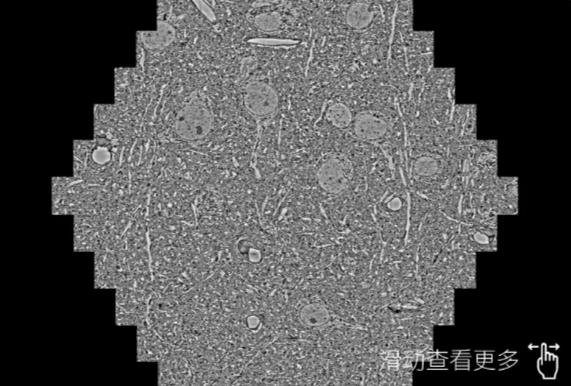

鼠脑切片。左图使用中山蔡司中山扫描电镜MultiSEM706对165μmx143pm面积区域成像,耗时仅需1.5秒。右图为鼠脑切片中30μm区域放大效果。样品由芝加哥大学B.Kasthuri提供。

使用蔡司高速中山扫描电镜MultiSEM对1mm²人脑皮层组织进行高分辨成像,并对其中的各种细胞结构进行三维重构分析。左图展示了2x3mm²组织平面中锥体神经元的三维重构效果。右图显示了局部体积神经元三维重构。图像由哈佛大学chtman实验室提供,渲染图由D. Berger 制作。